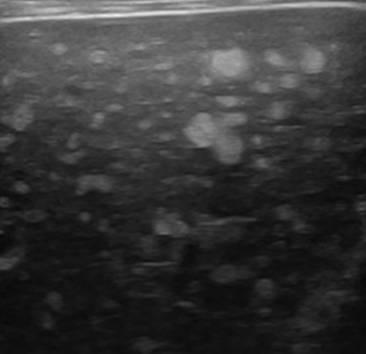

Hamartoma đường mật

» Thông tin: Nam giới – 39 tuổi.

» Lâm sàng: Kiểm tra sức khỏe.